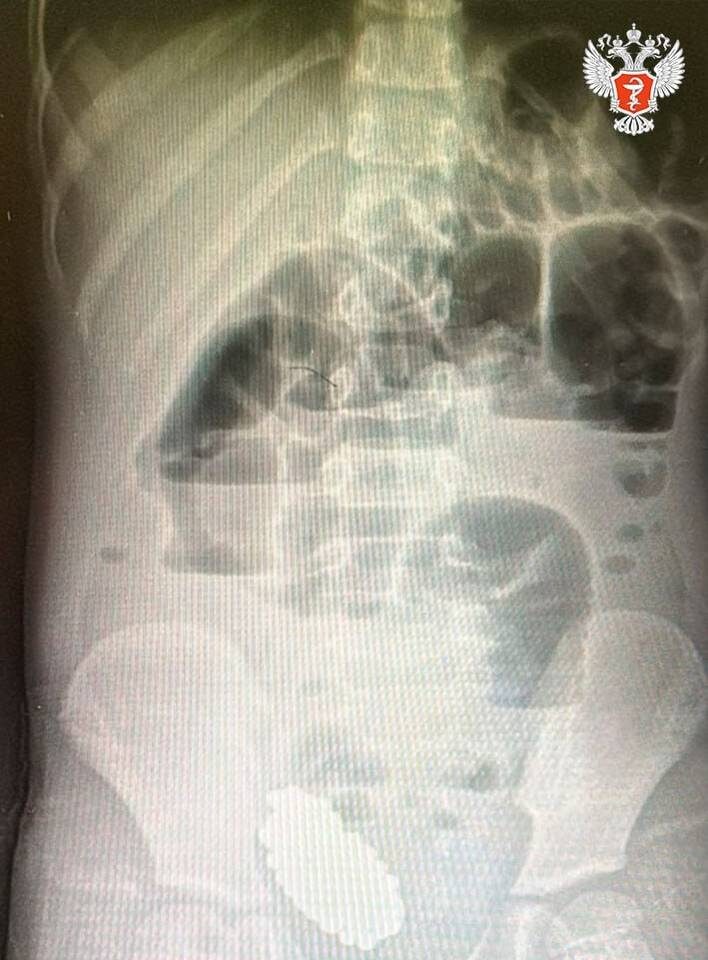

В ходе обследования врачи выявили кишечную непроходимость, вызванную инородным телом. Рентген показал массивный конгломерат из 134 магнитных шариков, которые сдавливали стенки кишечника.